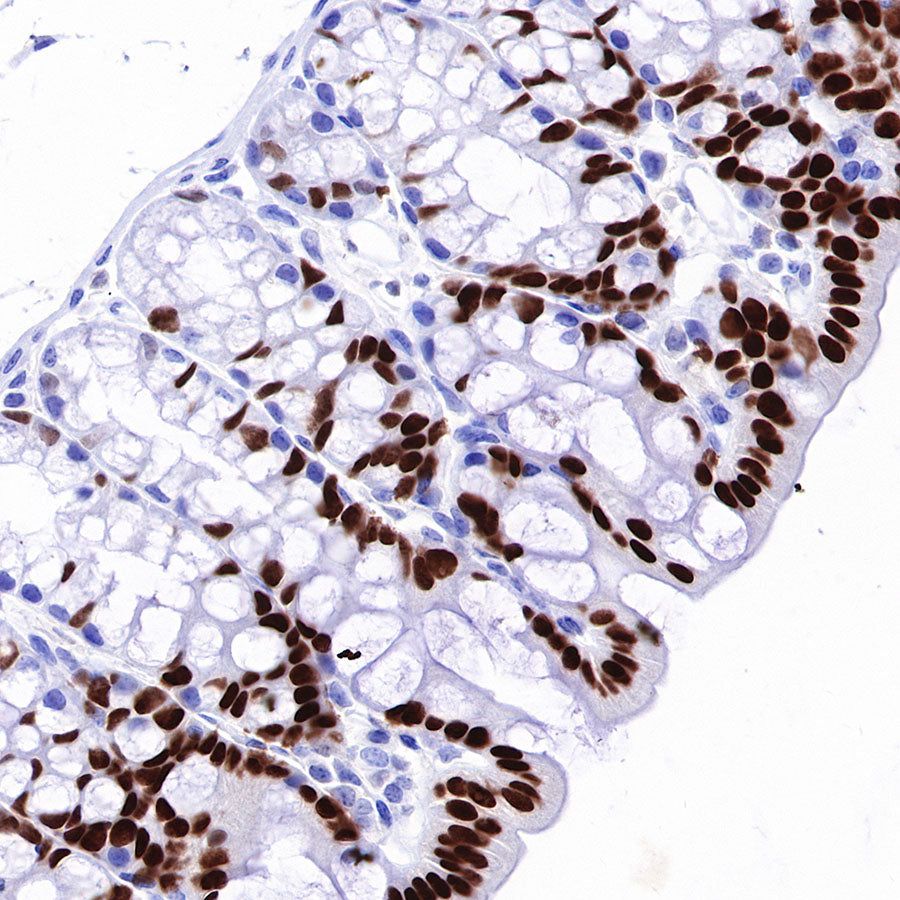

IHC shows positive staining in paraffin-embedded human colon. Anti-HNF4α antibody was used at 1/500 dilution, followed by a HRP Polymer for Mouse & Rabbit IgG (ready to use). Counterstained with hematoxylin. Heat mediated antigen retrieval with Tris/EDTA buffer pH9.0 was performed before commencing with IHC staining protocol.

IHC shows positive staining in paraffin-embedded human colon cancer. Anti-HNF4α antibody was used at 1/500 dilution, followed by a HRP Polymer for Mouse & Rabbit IgG (ready to use). Counterstained with hematoxylin. Heat mediated antigen retrieval with Tris/EDTA buffer pH9.0 was performed before commencing with IHC staining protocol.